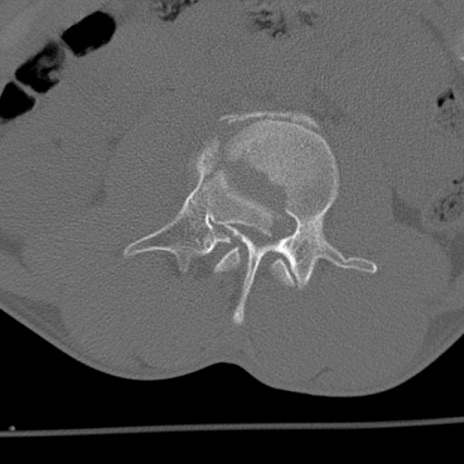

症例3 腰椎CT(横断像)

腰椎CT